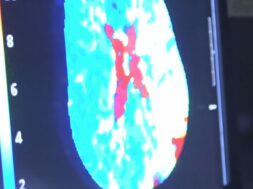

Όλο και περισσότερες μελέτες περιγράφουν την ευρεία νευρολογική σημειολογία που σχετίζεται με λοίμωξη COVID-19. Με άρθρο τους στο επιστημονικό περιοδικό The Lancet Neurology 19(9);P713-715 (COVID-19 related stroke in young individuals) οι J.T. Fifi και J. Mocoo σχολιάζουν ειδικά την εμφάνιση οξέων εγκεφαλικών συμβαμάτων σε νέους ασθενείς με λοίμωξη COVID-19.

Σύμφωνα με τα τρέχοντα δεδομένα, ο νέος κορωνοϊός SARS-CoV-2 είναι πολύ πιθανότερο να προκαλέσει θρομβωτικά αγγειακά συμβάματα, συμπεριλαμβανομένου και του αγγειακού εγκεφαλικού επεισοδίου, συγκριτικά με άλλους κορωνοϊούς και άλλες ιώσεις. Πιο συγκεκριμένα, ο κίνδυνος για αγγειακό εγκεφαλικό επεισόδιο είναι 7.6 φορές υψηλότερος σε ασθενείς με COVID-19 συγκριτικά με ασθενείς που πάσχουν από γρίπη. Το αναφερόμενο ποσοστό των ασθενών με λοίμωξη COVID-19 που εμφανίζουν αγγειακή εγκεφαλική νόσο κυμαίνεται από 1% έως 6%, το οποίο βεβαίως μεταφράζεται σε χιλιάδες ασθενείς καθώς τα συνολικά κρούσματα παγκοσμίως συνεχίζουν να αυξάνονται.

Οι προτεινόμενοι παθοφυσιολογικοί μηχανισμοί συμπεριλαμβάνουν την κατάσταση υπερπηκτικότητας λόγω της συστηματικής φλεγμονής και της «καταιγίδας κυτταροκινών», την μετα-λοιμώδη ανοσολογική απόκριση, καθώς και την άμεση βλάβη του ενδοθηλίου των αγγείων από το SARS-CoV-2 (ενδοθηλίτιδα ή ενδοθηλιοπάθεια), η οποία οδηγεί σε θρόμβωση των αγγείων, συμπεριλαμβανομένων και των αγγείων του εγκεφάλου.

Κατά τη χρονική περίοδο 23 Μαρτίου έως 7 Απριλίου 2020 οι συγγραφείς του άρθρου, που εργάζονται σε νοσοκομεία στη Νέα Υόρκη των ΗΠΑ αναφέρουν ότι 5 ασθενείς μικρότεροι των 50 ετών προσήλθαν με αγγειακό εγκεφαλικό επεισόδιο σε μεγάλο αγγείο του εγκεφάλου. Όλοι ήταν θετικοί στον νέο κορωνοϊό SARS-CoV-2 ενώ δεν είχαν όλοι παράγοντες κινδύνου για αγγειακά συμβάματα. Επιδημιολογικά, αυτό αποτελεί μια αύξηση των εγκεφαλικών επεισοδίων σε αυτή την ηλικιακή ομάδα κατά 7 φορές συγκριτικά με τα προηγούμενα χρόνια.

Η εργαστηριακή εικόνα των ασθενών ήταν ενδεικτική μιας κατάστασης υπερπηκτικότητας. Αυτή η παρατήρηση οδηγεί στη θεωρία ότι η λοίμωξη από το νέο κορωνοϊό SARS-CoV-2 πιθανότατα σχετίζεται με την εμφάνιση αγγειακού εγκεφαλικού επεισοδίου σε αυτούς τους νέους ασθενείς. Επιπλέον δεδομένα από άλλες ερευνητικές ομάδες στη Νέα Υόρκη των ΗΠΑ αλλά και στο Παρίσι της Γαλλίας δείχνουν ότι ασθενείς με COVID-19 που εμφανίζουν εικόνα αγγειακού εγκεφαλικού επεισοδίου έχουν μέση ηλικία τα 59 έτη, ενώ η μέση ηλικία των ασθενών αυτών χωρίς COVID-19 είναι τα 74 έτη.

Συμπερασματικά, όλο και περισσότερα δεδομένα υποδεικνύουν την ύπαρξη συσχέτισης μεταξύ της λοίμωξης COVID-19 και της εμφάνισης αγγειακού εγκεφαλικού επεισοδίου σε νέους ασθενείς που δεν έχουν άλλους τυπικούς παράγοντες κινδύνου για αγγειακή νόσο. Οι ερευνητές υποστηρίζουν ότι σε κατά τα λοιπά υγιείς νέους ασθενείς που προσέρχονται με αγγειακό εγκεφαλικό επεισόδιο κατά της διάρκεια της πανδημίας COVID-19 θα πρέπει να γίνεται έλεγχος ανίχνευσης του νέου κορωνοϊού SARS-CoV-2.

Επιπλέον ασθενείς με διεγνωσμένη λοίμωξη COVID-19 και ήπια συμπτώματα που εμφανίζουν νέα νευρολογικά σημεία ή/και συμπτώματα θα πρέπει να διερευνώνται πλήρως για αγγειακό εγκεφαλικό σύμβαμα.